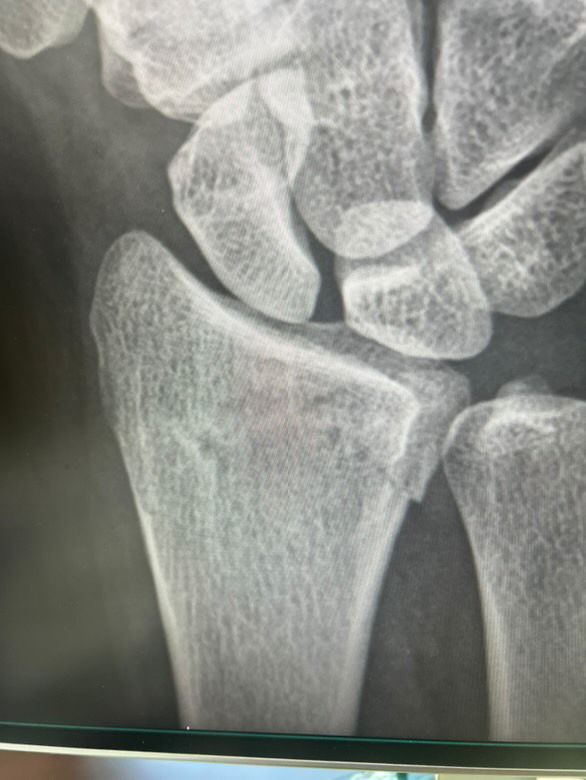

• 1번 째 사진

• 엑스레이 사진을 보았을 때 요골 골절이 있어 보입니다. 해당 엑스레이 사진만 놓고 정확하게 어떻다 이야기를 하기는 어렵습니다만, 개인적으로 보기에도 수술적 치료가 필요할 것으로 사료됩니다. 손목 같은 경우 많이 사용하는 부위이며 기능이 잘 유지되도록 하기 위해서는 적극적으로 치료가 필요합니다.